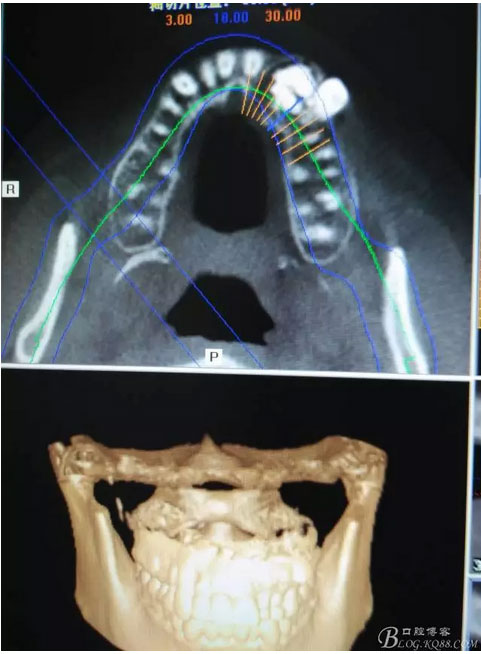

患者、女、曹xx、26歲,已婚。主訴:左側(cè)前牙區(qū)牙齦上有一疙瘩,要求治療。??茩z查:左側(cè)乳Ⅱ、Ⅲ滯留,頸部楔形缺損,探針不敏感。左側(cè)乳Ⅱ、Ⅲ唇側(cè)粘膜膨隆,表面結(jié)節(jié)狀,捫診質(zhì)地堅(jiān)硬,無波動(dòng)。CBCT檢查:左側(cè)乳Ⅱ、Ⅲ上方有一范圍約2.0x2.8cm的囊性改變,囊腔內(nèi)大量致密鈣化團(tuán)塊,密度高。22位于囊腔上方骨質(zhì)內(nèi),23移位至24上方區(qū)。診斷:1.牙瘤?2.牙瘤伴發(fā)囊腫?治療計(jì)劃:建議手術(shù)摘除?;颊咄馐中g(shù),并建議盡量保留左側(cè)乳Ⅱ、Ⅲ簽知情同意書。

圖1。術(shù)前的CBCT影像檢查:22位于鼻底下方,23位于24、25的根方。左側(cè)乳Ⅱ、Ⅲ根方顯示囊性改變,囊腔內(nèi)大量致密鈣化團(tuán)塊,密度高。